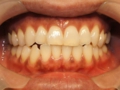

オフィスホワイトニング1日8回照射

➡

オフィスホワイトニング1日だけの症例です。

詰め物や被せ物がないのでバランス良く白くなりました。

当院のオフィスホワイトニングは薬液を使い切るまで照射回数フリーなので頑張っていただければ一日で白さを実感いただけます。